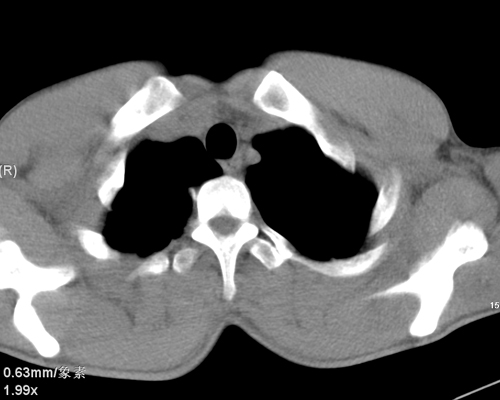

标题: CT24548:男 31 咳嗽 咯血一天 行CT检查 [打印本页]

标题: CT24548:男 31 咳嗽 咯血一天 行CT检查

ct考虑结核 但化验结果示白细胞总数 淋巴均正常,血沉7mm/h不快,请看看结核 支扩还是其他

右肺上叶尖端,后段下叶背段结核伴空洞形成

右肺继发性肺结核伴空洞形成!

右肺继发性肺结核伴右肺下叶背段空洞形成。